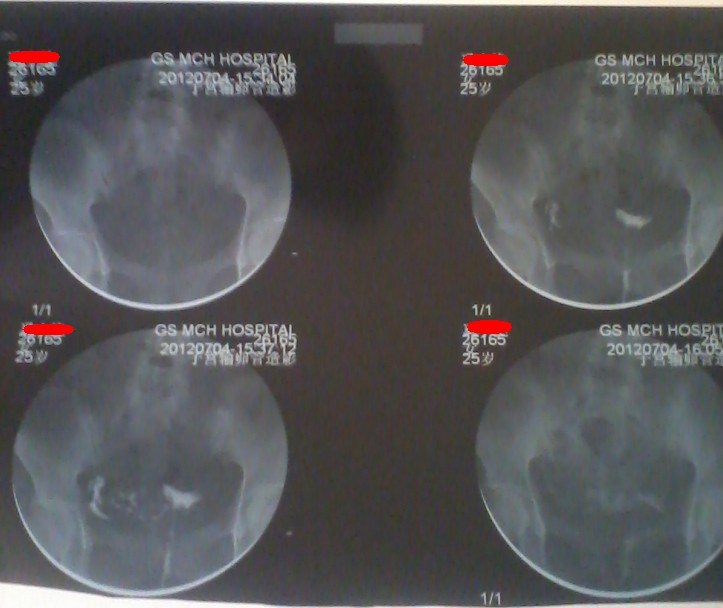

我是7月4日做的输卵管造影,结果是:左侧完全阻塞,右侧通畅,请问可以怀孕吗? 点击展开 匿名用户 2012-07-05 12:35 为您推荐: 其他回答 也有一半的几率怀孕,不用担心。 要不另一侧积极治疗。 匿名用户 2012-07-05 14:19 你好 ,只要有一侧是通畅的,就会排卵,是可以怀孕的 , 匿名用户 2012-07-05 13:33 一侧通有受孕的可能,几率就会小些 栾以晴_OaR0 2012-07-05 13:00 不一定! 匿名用户 2012-07-05 12:44 相关问题 今天做了输卵管造影,一侧通畅一侧积液,不知道能怀孕吗?急,急,急… 性生活5年,男方精液常规检查无异常,女方输卵管造影无阻塞,有正常卵泡发育及排卵;宫颈粘液抗精子抗体 做了造影后是两个月后怀孕吗